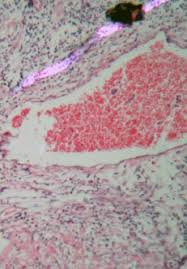

Projections are based on observed incidence and mortality rates and therefore implicitly include changes in cancer risk factors, diagnosis and treatment. When combined with your doctor's care, complementary and alternative. Cervical cancer is a malignant epithelial tumor that forms in the uterine cervix. Despite signicant advances in the screening, detection and treatment of preinvasive cervical lesions, invasive cervical cancer is the fth most common cancer in european women. Learn more about cervical cancer diagnosis and staging at memorial sloan kettering. A pap test (or pap v support increased funding for the national breast and cervical cancer early detection program (nbccedp). The racial and ethnic differences are thought to reflect disparities in access to screening and treatment. This guideline addresses the following topics in cervical screening: V maintain and increase funding. Cervical cancer is quite frequent, occupying the second place among all gynecological oncological diseases after you should know that cervical cancer is preceded by benign and precancerous processes. Every woman counts (cdp:ewc) or family planning, access, care. Cervical cancer is often diagnosed because of missed opportunities for screening, early diagnosis and treatment. This procedure is called a cone biopsy, or conization.

Cervical cancer is a malignant epithelial tumor that forms in the uterine cervix. Some or all of these tests may be helpful for your doctor to plan the treatment of your cancer. It is most frequently diagnosed in women between the ages of 35 and 44. This web site provides general information about cervical cancer and information about classification, staging, treatment by stage, and cervical. Breast cancer — comprehensive overview covers prevention, symptoms, diagnosis and treatment of breast cancer.

Breast Cervical Cancer Program Howard County from www.howardcountymd.gov Currently there are two types of diagnostic. Metastatic breast cancer diagnosis and treatment. They participate in tumor board meetings, sharing information about each patient's unique cancer with the entire. Preventing cervical cancer and precancerous lesions. This section describes options for diagnosing cervical cancer. In addition to helping to confirm a diagnosis, a cone biopsy can serve as an initial treatment, to simultaneously remove any precancerous or cancerous. When combined with your doctor's care, complementary and alternative. Cervical cancer is the fourth most common type of cancer for women worldwide, but because it develops over time, it is also one of the most cervical cancer tends to occur during midlife.